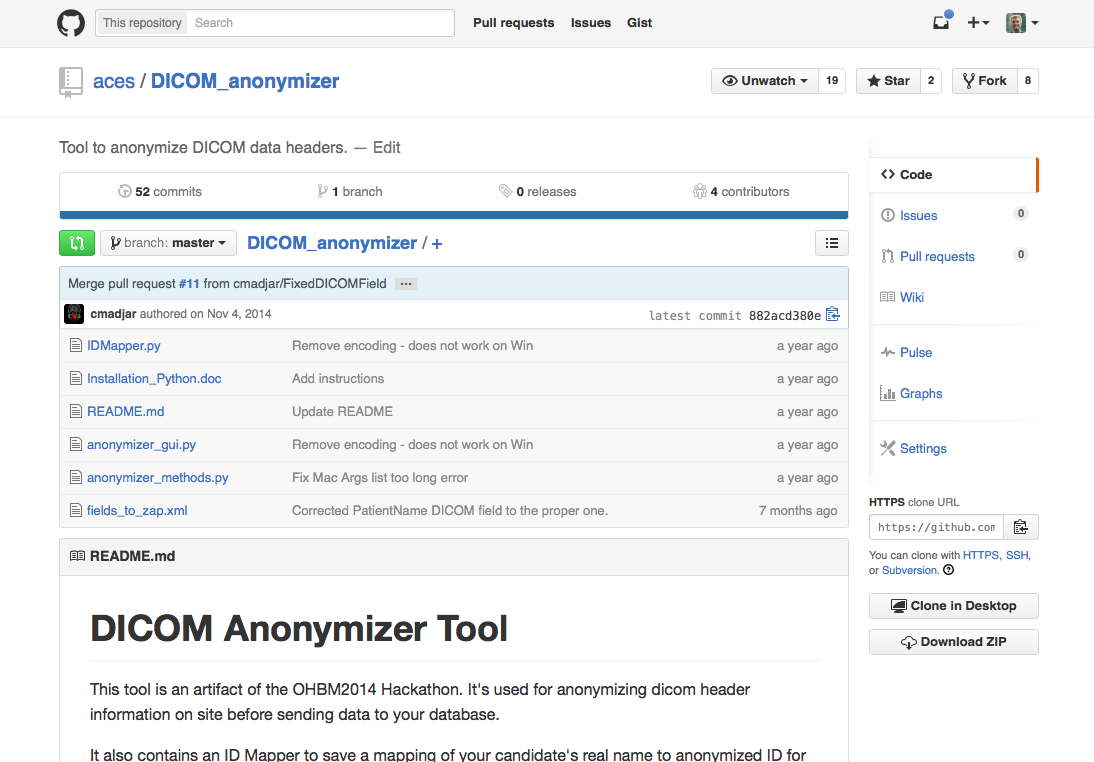

LORIS - Github - Open Source

https://github.com/aces/Loris

LORIS - Github Usage

Enhanced DICOM anonymization

- Going dcmtk free -- PYDICOM

- CONDA

- Satra knows everything!!

Enhanced DICOM anonymization